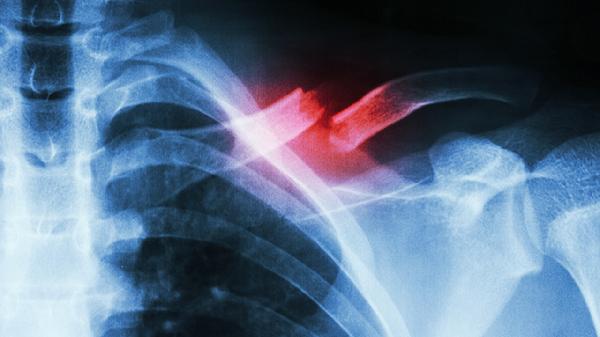

肋骨骨折加速康复,这些食物不能错过!

肋骨骨折的康复过程中,合理的饮食选择可以加速愈合,同时避免某些食物有助于减少炎症和感染风险。高蛋白质、富含维生素C和钙的食物是肋骨骨折康复的关键。